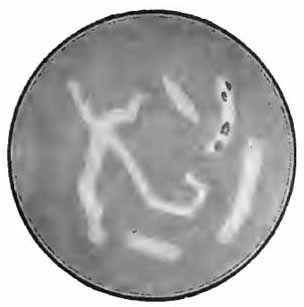

Sputum from a case of actinomycosis

FIG. 8.—Sputum from a case of actinomycosis; stained (Jakob).

5. Actinomyces Bovis (Ray-fungus).—In the sputum of pulmonary actinomycosis and in the pus from actinomycotic lesions elsewhere small, yellowish, "sulphur" granules can be detected with the unaided eye. The fungus can be seen by crushing one of these granules between slide and cover, and examining with a low power. It consists of a network of threads having a more or less radial arrangement, those at the periphery presenting club-shaped extremities (Fig. 8). This organism, also called Streptothrix actinomyces, apparently stands midway between the bacteria and the molds. It stains by Gram's method.

[p. 32] Actinomycosis of the lung is rare. The clinical picture is that of tuberculosis.